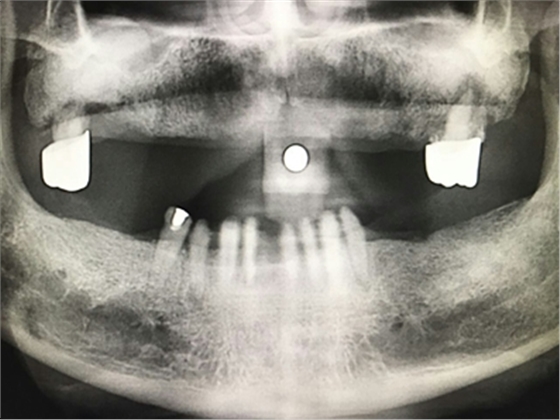

毛國斌種植病例——群討論分享